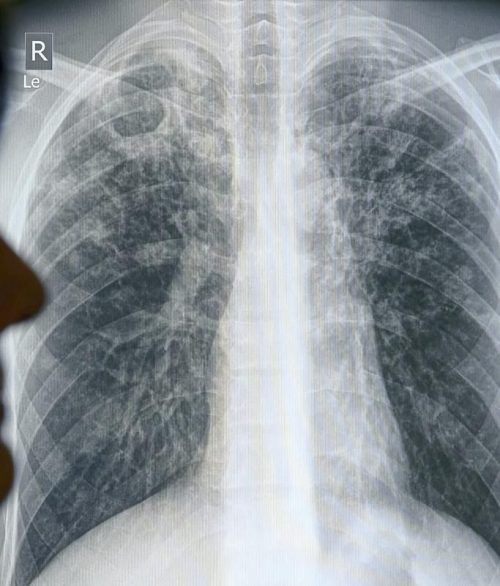

Das Röntgenbild eines Tuberkulosepatienten. © Jensen/dpa